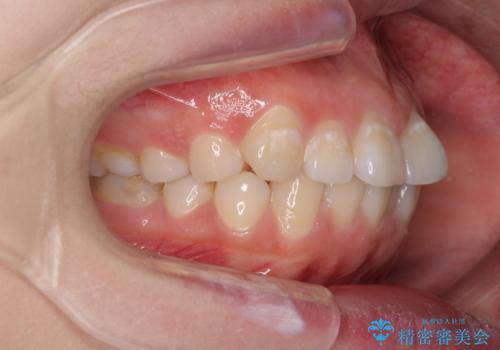

- 前歯のデコボコを気にして来院された患者様です。

当初は口元の突出感はあまり気にされていない様子だったので、インビザラインによる非抜歯矯正をお勧めしたが、ふっくらとした口元を改善したいとのことで、積極的に口元の突出感を改善することとしました。

上下左右第一小臼歯4本の抜歯を行い、ワイヤー装置による矯正治療を行うこととしました。